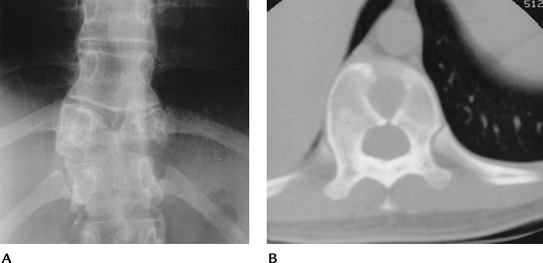

Congenital Anomalies: Segmentation Anomalies

-

Segmentation anomalies of the vertebrae include hemivertebra, block vertebrae, and butterfly vertebrae. Scoliosis may result.

Vertebral body anomalies are detected on routine radiographs. MRI may be required to exclude other spinal anomalies.

![]() |

|

FIGURE 3-74 Butterfly vertebra. (A) AP radiograph of the spine demonstrating a butterfly vertebra at T10. (B) Axial CT image shows the midline segmentation of the vertebral body.